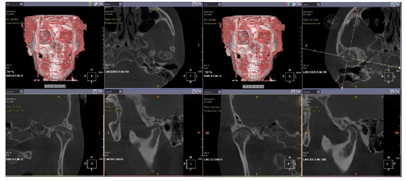

面充填物,未见根充物,根尖无明显异常(图4)。CBCT示:双侧髁突形态不对称,左侧髁突表面中央凹陷,余骨质未见异常(图5)。

影像学检查:曲面断层片及CBCT示,上下颌骨可见多个钛板内固定,12、24、34、44牙缺失。余骨质未见确切异常改变(图12,图13)。